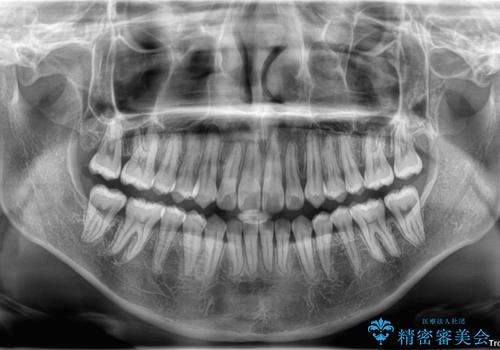

患者様の協力もあり、およそ1年間で治療を完了。スムーズな歯の移動を実現しました。

上下の正中(真ん中のライン)もずれることなく、バランスの取れた美しい歯並びに。笑顔に自信を持てる仕上がりとなりました。